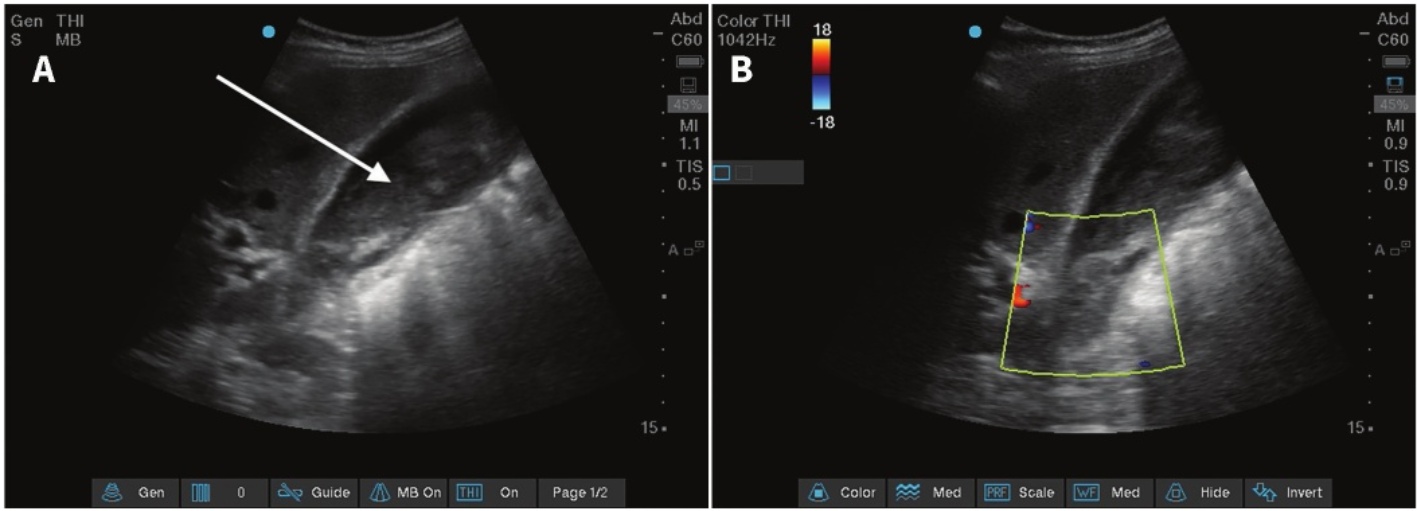

Figure 3. (A) Echocardiography reveals an endovascular aortic stent, with the maximum diameter of the aortic sac measuring 4.86 cm. (B) On color Doppler flow imaging, an endoleak originating from a patent lumbar artery with a diameter of 0.33 cm is visualized, which is located at the left inferior margin of the aneurysm sac

3. (A) 超声心动图显示一个主动脉内支架,其主动脉囊最大直径为4.86厘米。(B) 在彩色多普勒血流成像中,可见来自一条直径为0.33厘米的开放腰动脉的内漏,位于动脉瘤囊的左下边缘